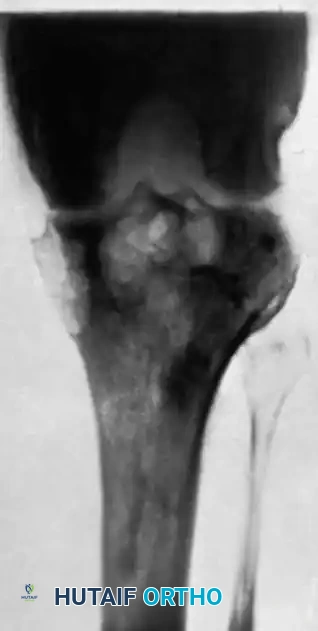

The Knee

The knee is the most commonly affected appendicular joint. Patients present with a boggy, swollen joint, severe quadriceps atrophy, and a flexion contracture.

If diagnosed early (synovial stage), arthroscopic synovectomy combined with chemotherapy can preserve joint function. However, once the subchondral bone is compromised and the articular cartilage is destroyed (as demonstrated in the radiograph above), joint preservation is no longer viable.

Surgical Management: Knee Arthrodesis

For advanced destruction, knee arthrodesis provides a stable, painless limb.

1. Approach: A standard anterior midline incision with a medial parapatellar arthrotomy.

2. Debridement: Radical synovectomy and excision of the menisci, cruciate ligaments, and infected bone.

3. Bone Cuts: Flat cuts are made on the distal femur and proximal tibia to ensure maximum cancellous bone contact. The knee is positioned in 5 to 10 degrees of flexion and neutral mechanical alignment.

4. Fixation: An intramedullary nail or dual-plate construct is utilized for rigid biomechanical stability.